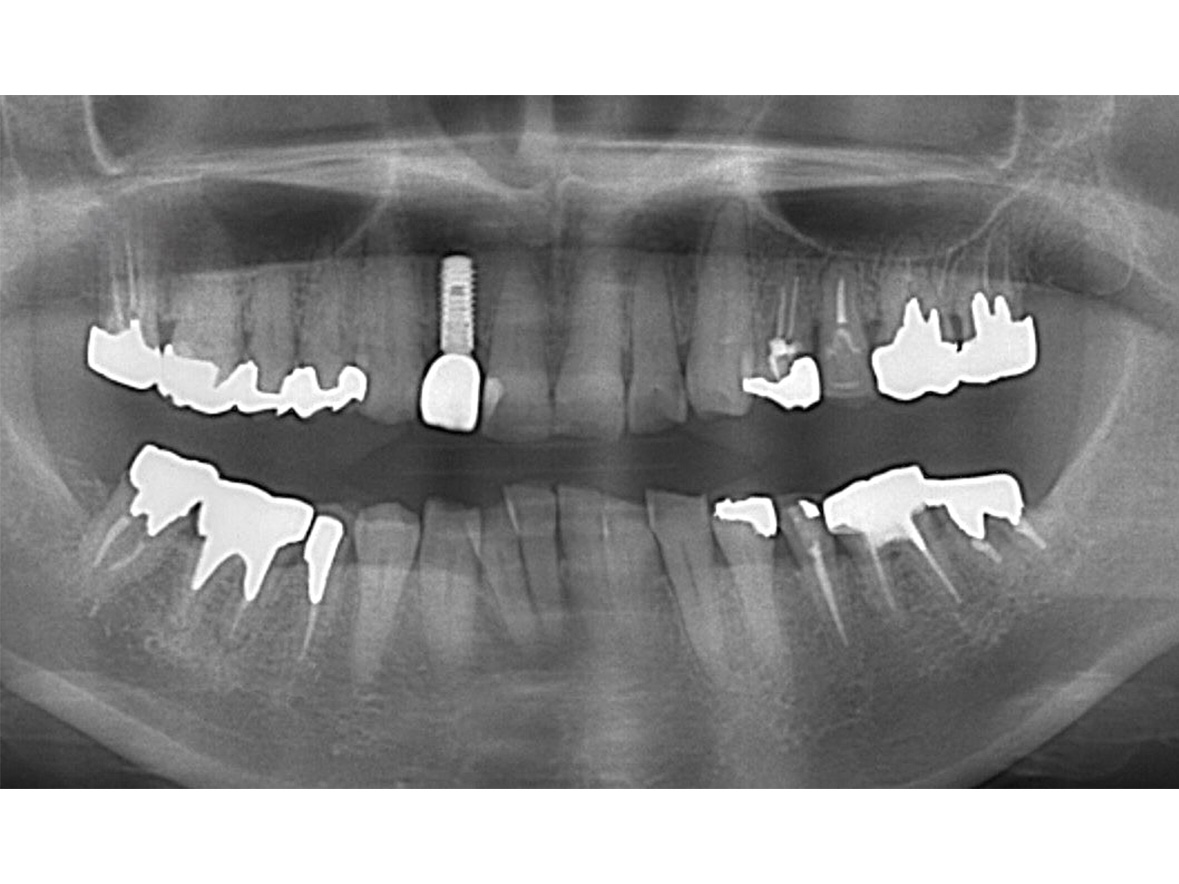

症例2

患者様の年齢 70代女性 主訴 入れ歯が痛い 噛みにくい 治療内容 上顎オールオン6

下顎臼歯部3本インプラント治療

抜歯即時インプラント埋入後3ヶ月の待機期間後、ジルコニアによる上部構造装着費用 456万円 治療期間・通院回数 6ヶ月/8回 デメリット・リスク 外科処置に伴う痛み・腫れ・出血・合併症の可能性があります。 -